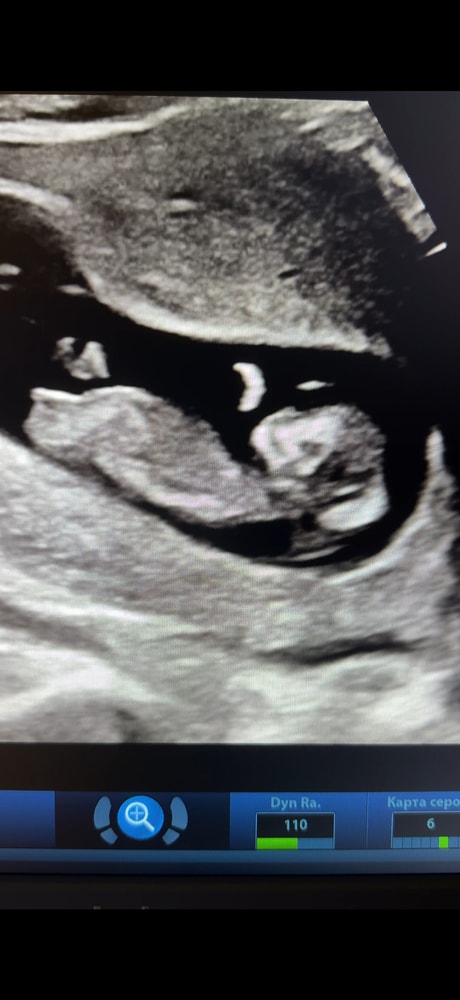

Половой бугорок параллельно спинке - девочка) Ну я такой же эксперт как и вы) Даже Узисты на этом сроке ошибаются. Пока что всё 50/50

Если я правильно вижу, то малыш лежит боком к нам) и пол невозможно разглядеть )

Не тот ракурс для определения пола))